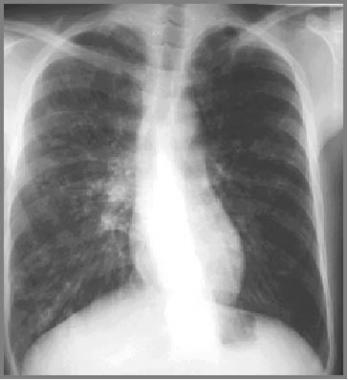

图3 囊性纤维化患者双侧支气管扩张 , 并伴有左上叶肺不张

图5 27岁患者仅有轻微症状 , 显示为支气管壁增厚、双侧小结节状浑浊和脊柱侧弯 。